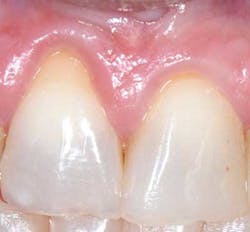

Depending on the severity and extent that the mucogingival defects present, we often administer a hybrid/combination therapy. Many of our patients previously experienced mucogingival grafting procedures at other offices, searched the Internet, or discussed with friends who have had soft-tissue grafts, and as a result they are extremely fearful of the dreadful “pizza burn” that one may experience after harvesting from the palate. As reported in the literature and confirmed clinically in our office, with the addition of an enamel matrix protein, patients consistently report minimal postoperative swelling and discomfort. This has been a huge game changer for our practice and will be for yours too (figure 3). (7)